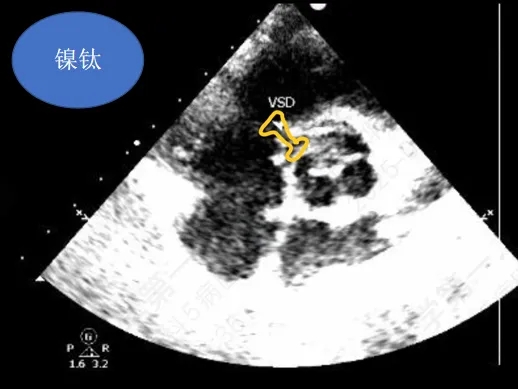

术前超声与DSA复测

VSD(膜周部):室间隔膜部瘤,左室面6.5mm,右室面呈“瘤样”结构,瘤体深度7mm,出口2mm。

形态与术前超声差别:

该病灶呈现为“长隧道、大瘤底、小出口”的细腰形态,且位置紧邻主动脉瓣与三尖瓣,解剖结构较为复杂。此形态特征使得可降解封堵器在植入过程中的定位与释放面临较大挑战。